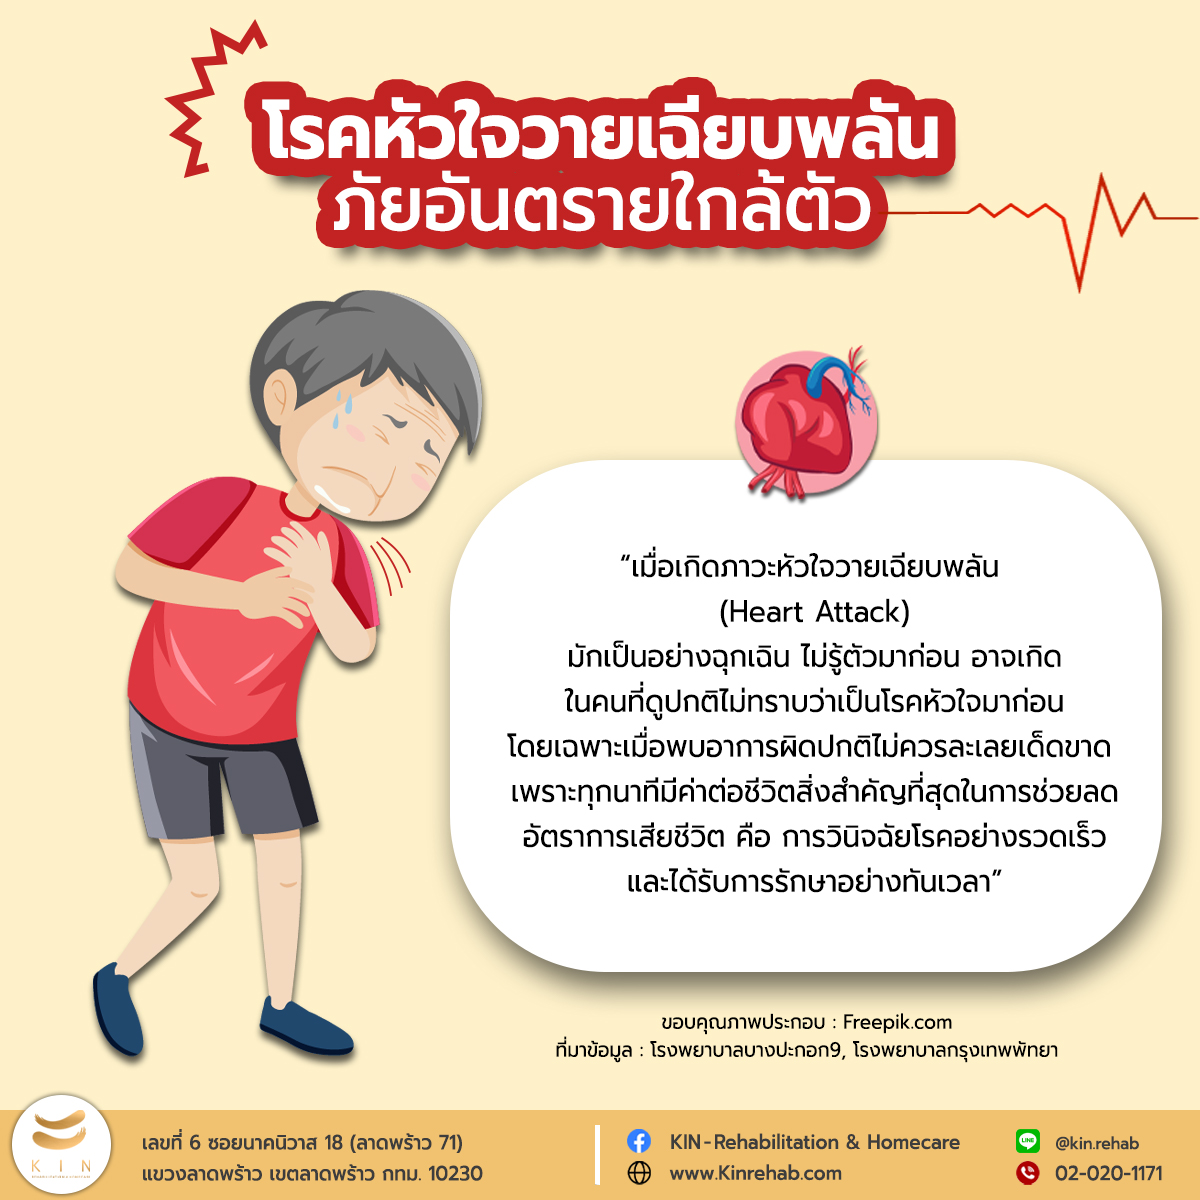

รู้ทันโรคหัวใจวายเฉียบพลัน คุณภาพ ภาพเอกซเรย์ 2555 – GotoKnow

รู้ทัน… ภาวะหัวใจล้มเหลว รู้จักโรคขี้เต็มท้อง!! “ตุ๊กตา จมาพร” เผยอาการและข้อห้ามทำ